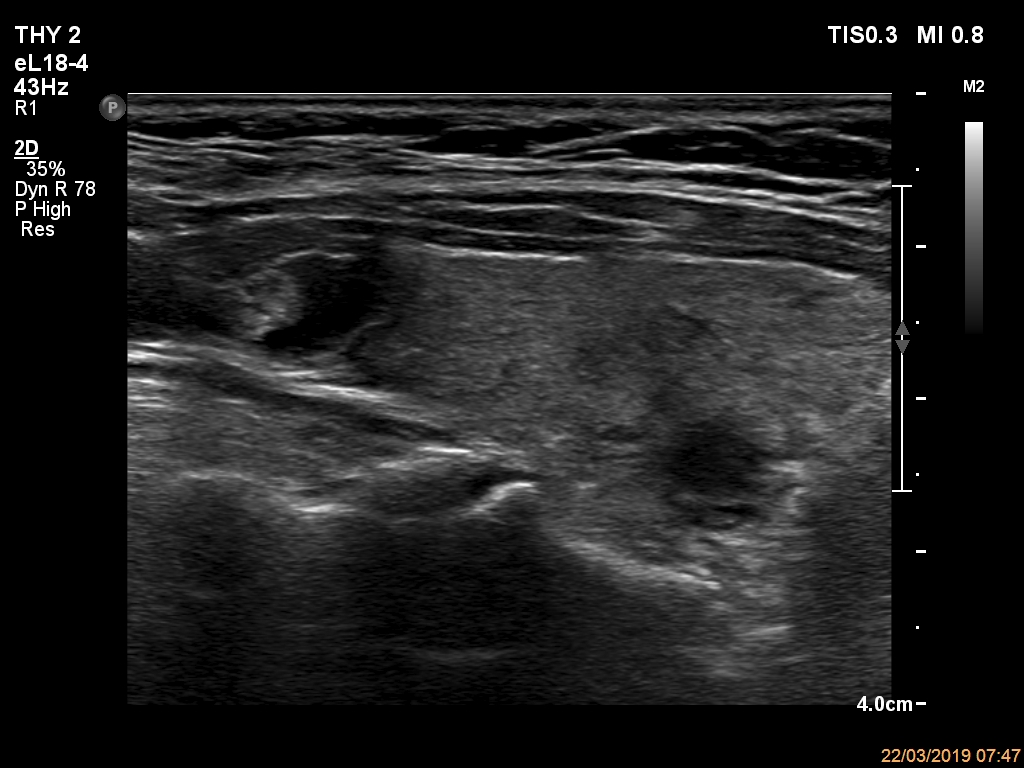

Elastography - case 2150 (ultrasonographic picture 4)

Right lobe, another longitudinal view. The echogenic figures in the upper nodule correspond to back wall figures caused by posterior enhanement. The almost completely cyst is impossible to categorize as peripheral or central.